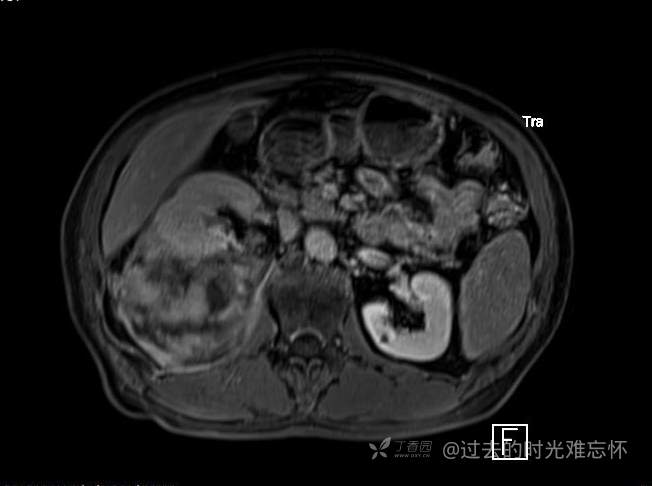

患者性别:男

患者年龄:73岁

主诉:咳嗽1月余。曾有血尿一次。后背部酸痛不适1-2年左右,无明显消瘦。

辅助检查:CT MRI

临床诊断:占位

治疗经过:手术

T2压脂

黏液样脂肪肉瘤 (12)